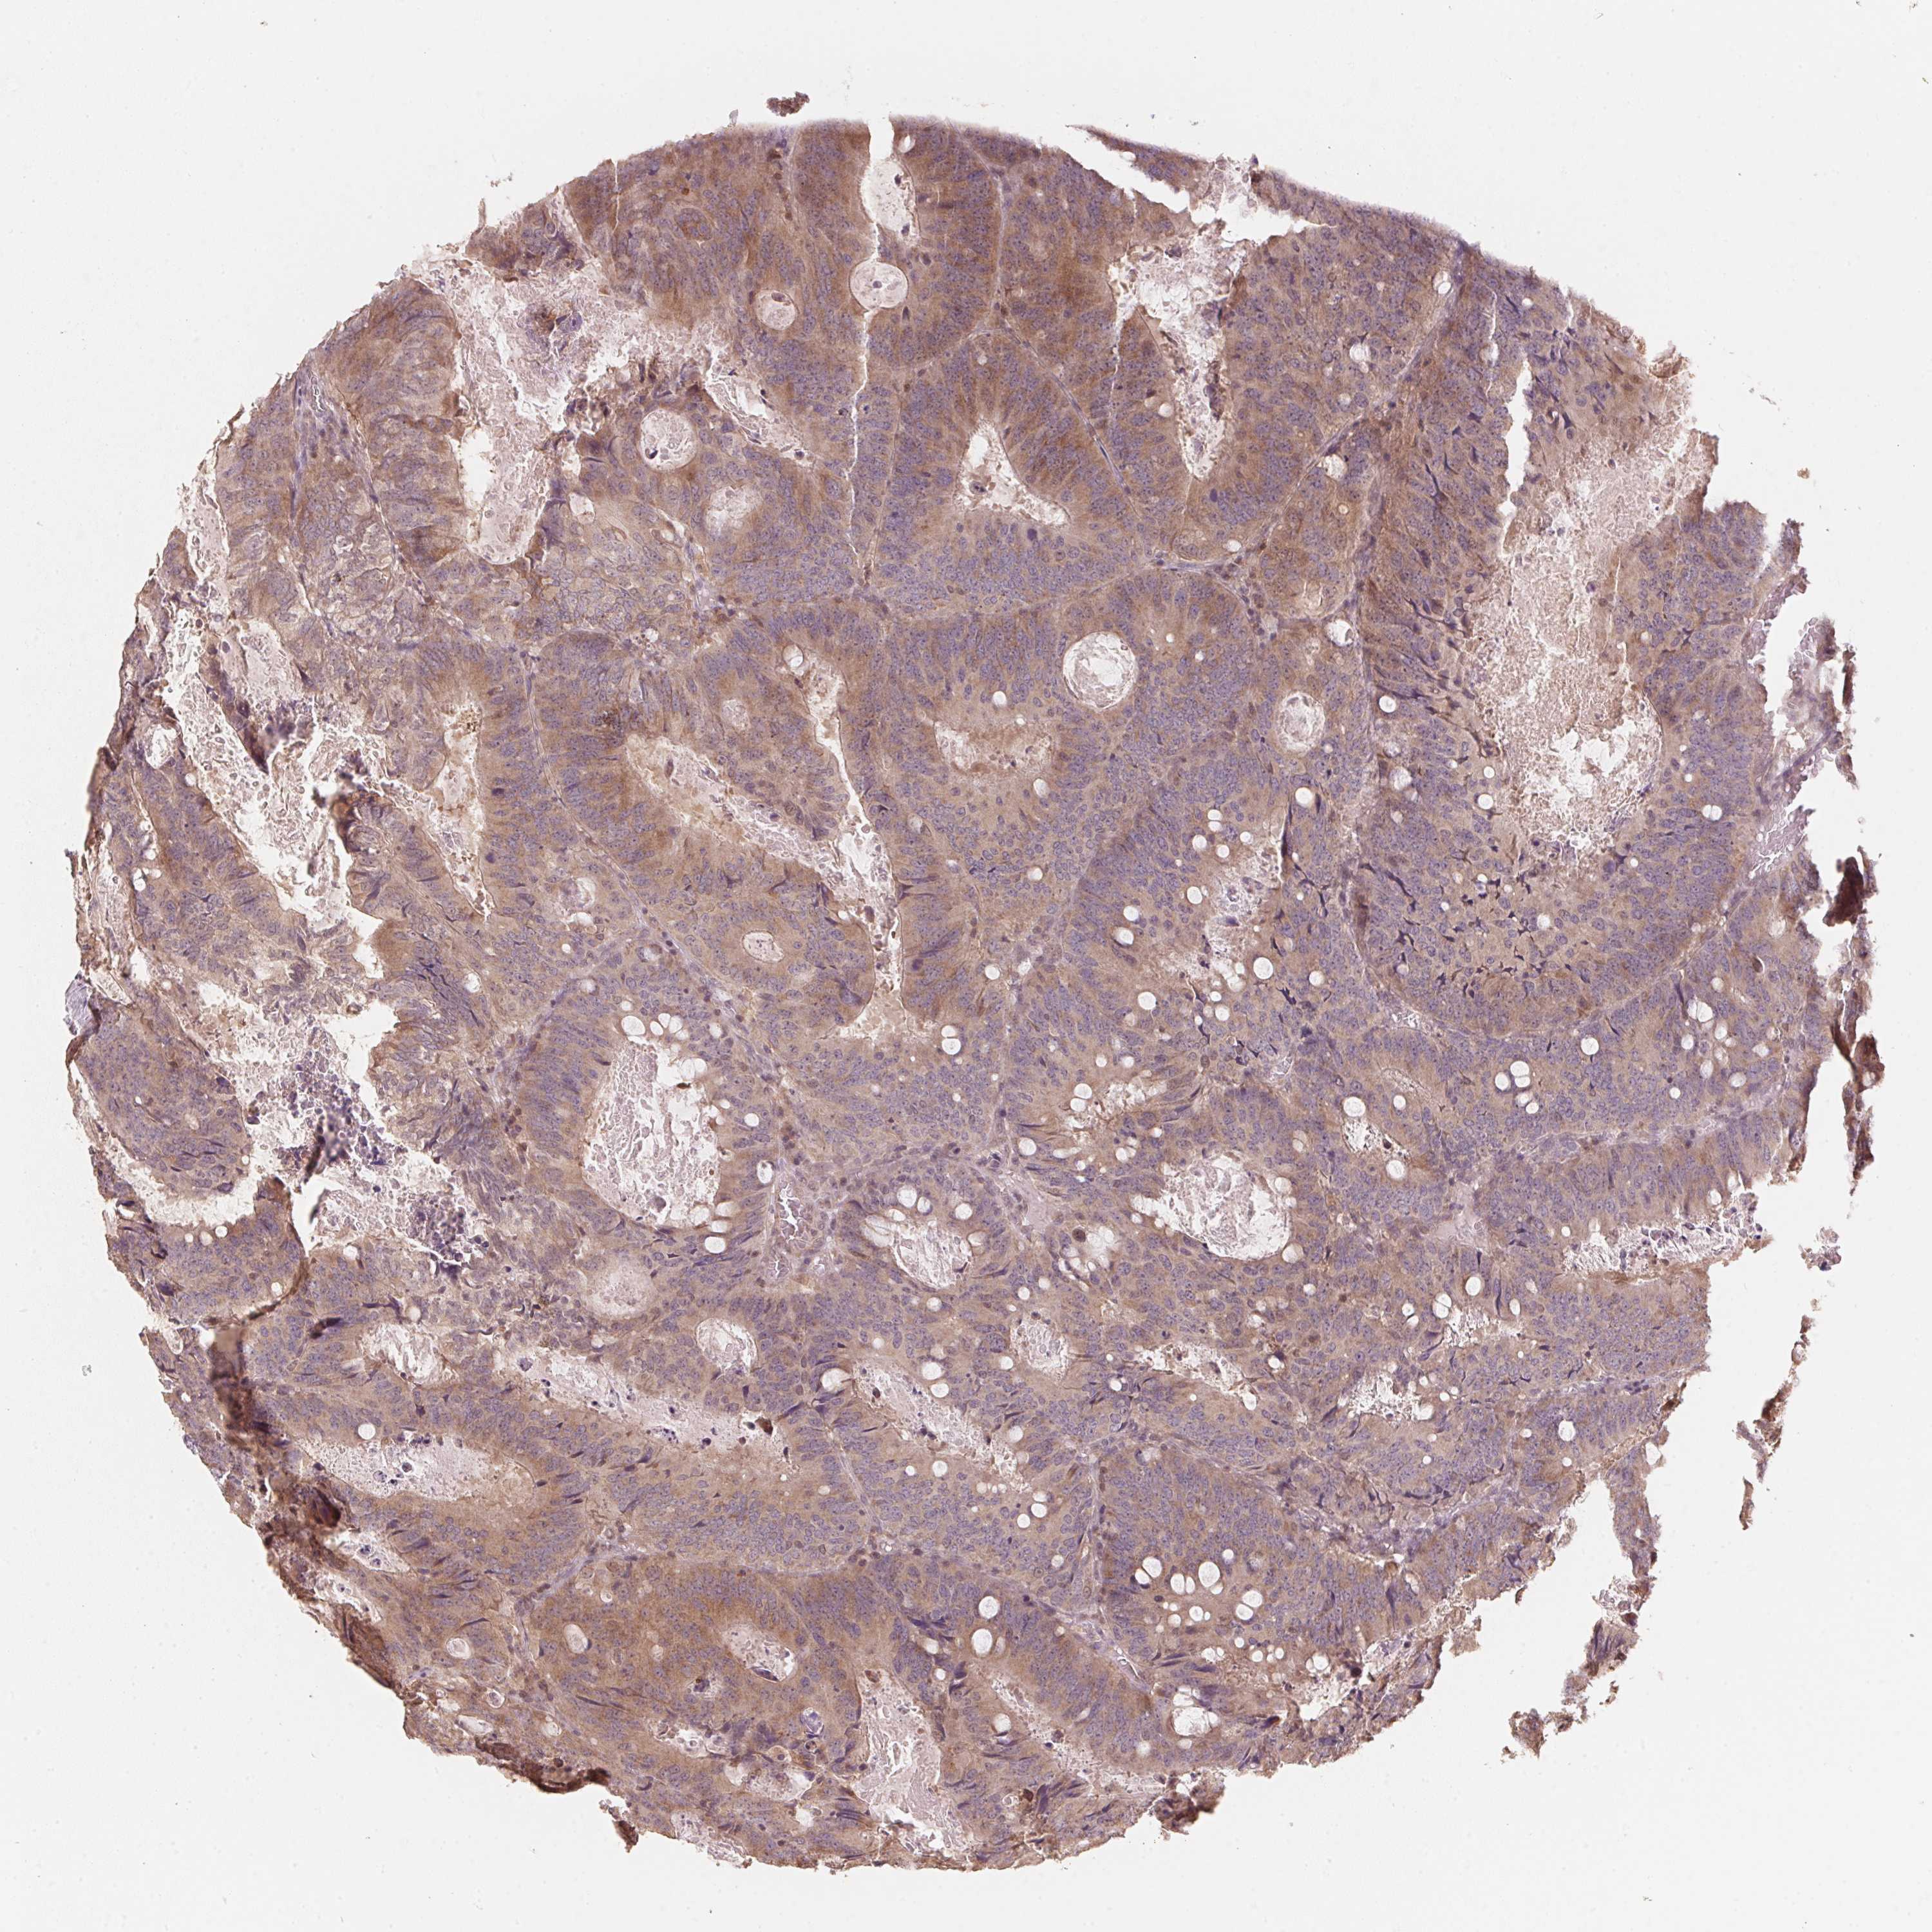

CANCER COLORECTAL CANCER Show tissue menu

Colorectal cancer

Human cancer

Colon adenocarcinoma